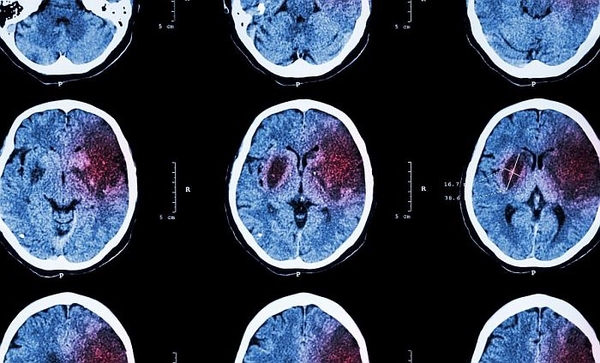

Khi một cục máu đông hoặc sự tích tụ của các mảng chất béo làm tắc động mạch dẫn đến não, sẽ ngăn chặn nguồn cung cấp máu và oxy đến một khu vực, gây tổn thương hoặc chết các tế bào não. Đây được gọi là đột quỵ do thiếu máu cục bộ và là loại đột quỵ phổ biến nhất.

Việc phục hồi một số chức năng não bị mất của một người sau đột quỵ do thiếu máu cục bộ thường được thực hiện thông qua phục hồi chức năng chuyên sâu, cho thấy não có thể tự phục hồi sau chấn thương. Tuy nhiên, cho đến nay, các cơ chế sửa chữa thần kinh cơ bản vẫn khó nắm bắt.